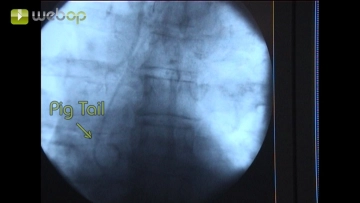

Após a inserção da prótese aórtica endoluminal relativamente rígida juntamente com o sistema de entrega, as marcações podem ocasionalmente desviar da posição real dos marcadores. Em casos de distâncias próximas entre a extremidade da prótese e a artéria subclávia ou tronco celíaco, como no exemplo do vídeo, uma DSA repetida é necessária antes de liberar o corpo da prótese para garantir que os lúmens dos vasos mencionados não sejam inadvertidamente ocluídos.